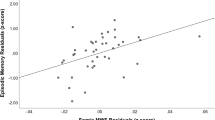

Independent of e4 status, Pearson’s correlation coefficients demonstrated that increased age is significantly correlated with shorter FBLs in the temporal lobe and UF, as well as decreased performance on tests of memory. See Table 4. A significant positive relationship between temporal FBL and memory scores was evident on the list learning task but no other cognitive indices. A significant positive relationship was also evident between semantic fluency and UF FBL of the left hemisphere but no other cognitive scores. No significant differences were observed between UF FBL of the right hemisphere and cognitive performance. See Table 5.